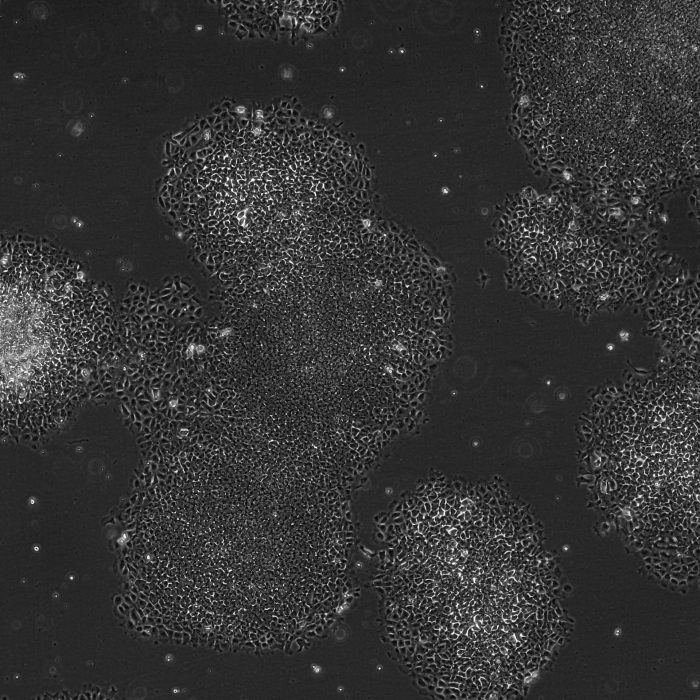

Microscopic visualisation of endoderm cellular structures

Definitive Endoderm derived from pluripotent stem cells can be leveraged to give rise to important tissues such as lung, liver, pancreas and intestines. For those tissues with established protocols, these cells can be used to create reproducible organoids, whilst for those without an established protocol they can be a robust, reproducible starting material for optimisation of culture conditions.